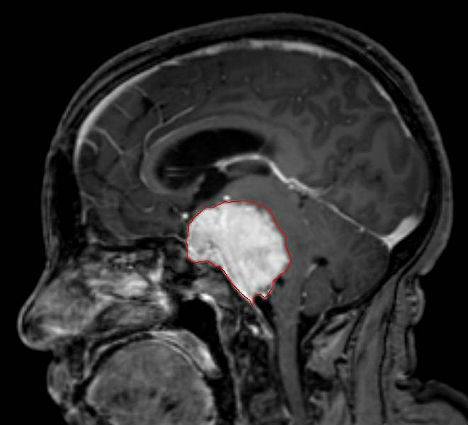

8. 细菌治疗癌症

在癌症治疗中,一种名为“产孢梭菌”的细菌可以用来输送药物,因为它具有直接命中肿瘤的功能。英国诺丁汉大学科学家尼吉尔-明顿教授发现,“产孢梭菌”只能生长于缺氧的环境中,如肿瘤的中心。当治疗癌症的药物注入到肿瘤中时,这种细菌可以帮助药物直接命中肿瘤细胞,而不会影响健康的组织。研究人员希望,到2013年将这种细菌治疗手段投入临床试验。